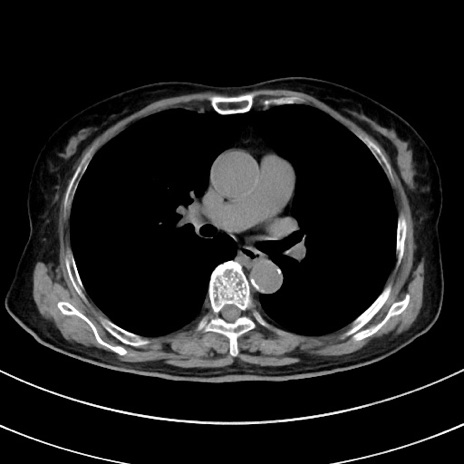

冠状断像

【症例】70歳代 女性

【主訴】心窩部痛

【現病歴】延髄病変の精査・加療にて神経内科入院中。本日より心窩部痛あり。

【身体所見】右下腹部を中心に圧痛と反跳痛あり。